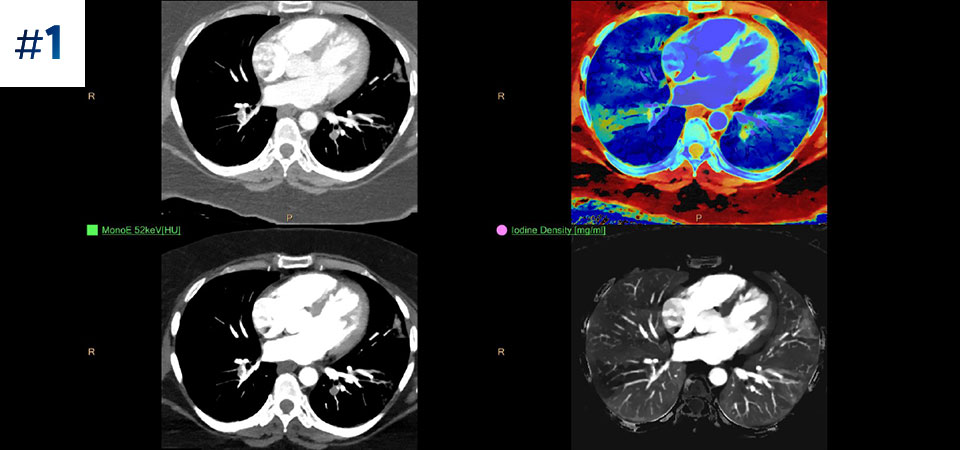

Nuestro CT con detección espectral de Philips, nos permite adquirir datos convencionales y espectrales en una sola exploración, sin cambios en nuestro flujo de trabajo actual.

Observe las diferencias entre un detector espectral CT y un CT Convencional

Aprenda sobre las ventajas del detector espectral CT